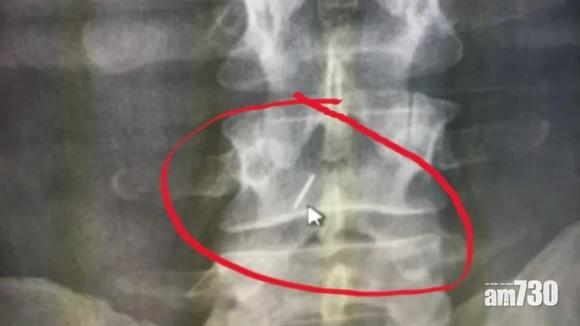

伊波利托展示X光片。(互聯網)

X光檢查顯示,幼針藏在脊椎(互聯網)

10多年後才發現的醫療失誤!加拿大安大略省女子伊波利托(Giovanna Ippolito)兩年多前開始覺得肩膊痛楚、右腳無力,2018年10月接受X光檢查,赫然發現脊椎藏著一支5厘米長的折斷幼針,「我只感到一陣陣刺痛」。伊波利托回想,多年來只接受過兩次背部注射,分別是2002年生仔、04年生女時,醫生在她背部打麻醉針做無痛分娩,而兩次生產都是在麥健時列治文山醫院(Mackenzie Richmond Hill Hospital),她懷疑其中一次,醫生誤把長針留在她體內。